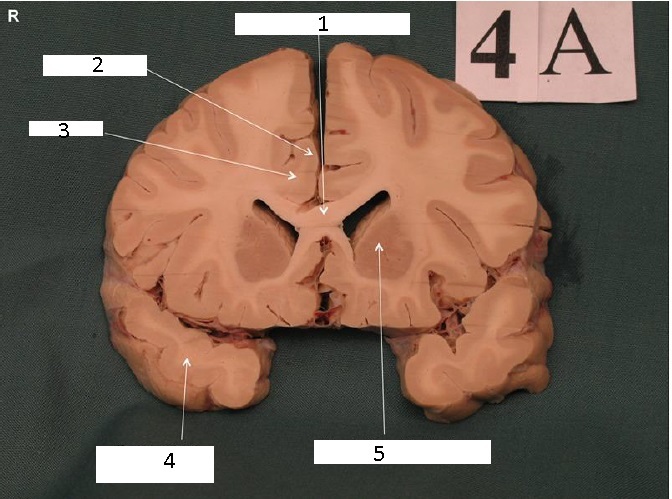

Genu of Corpus callosum

Lateral Ventricles

Identify 1

Head of Caudate Nucleus

Identify 2

Putamen

Identify 3

Cingulum

Identify 4

Temporal Lobe

Identify 5